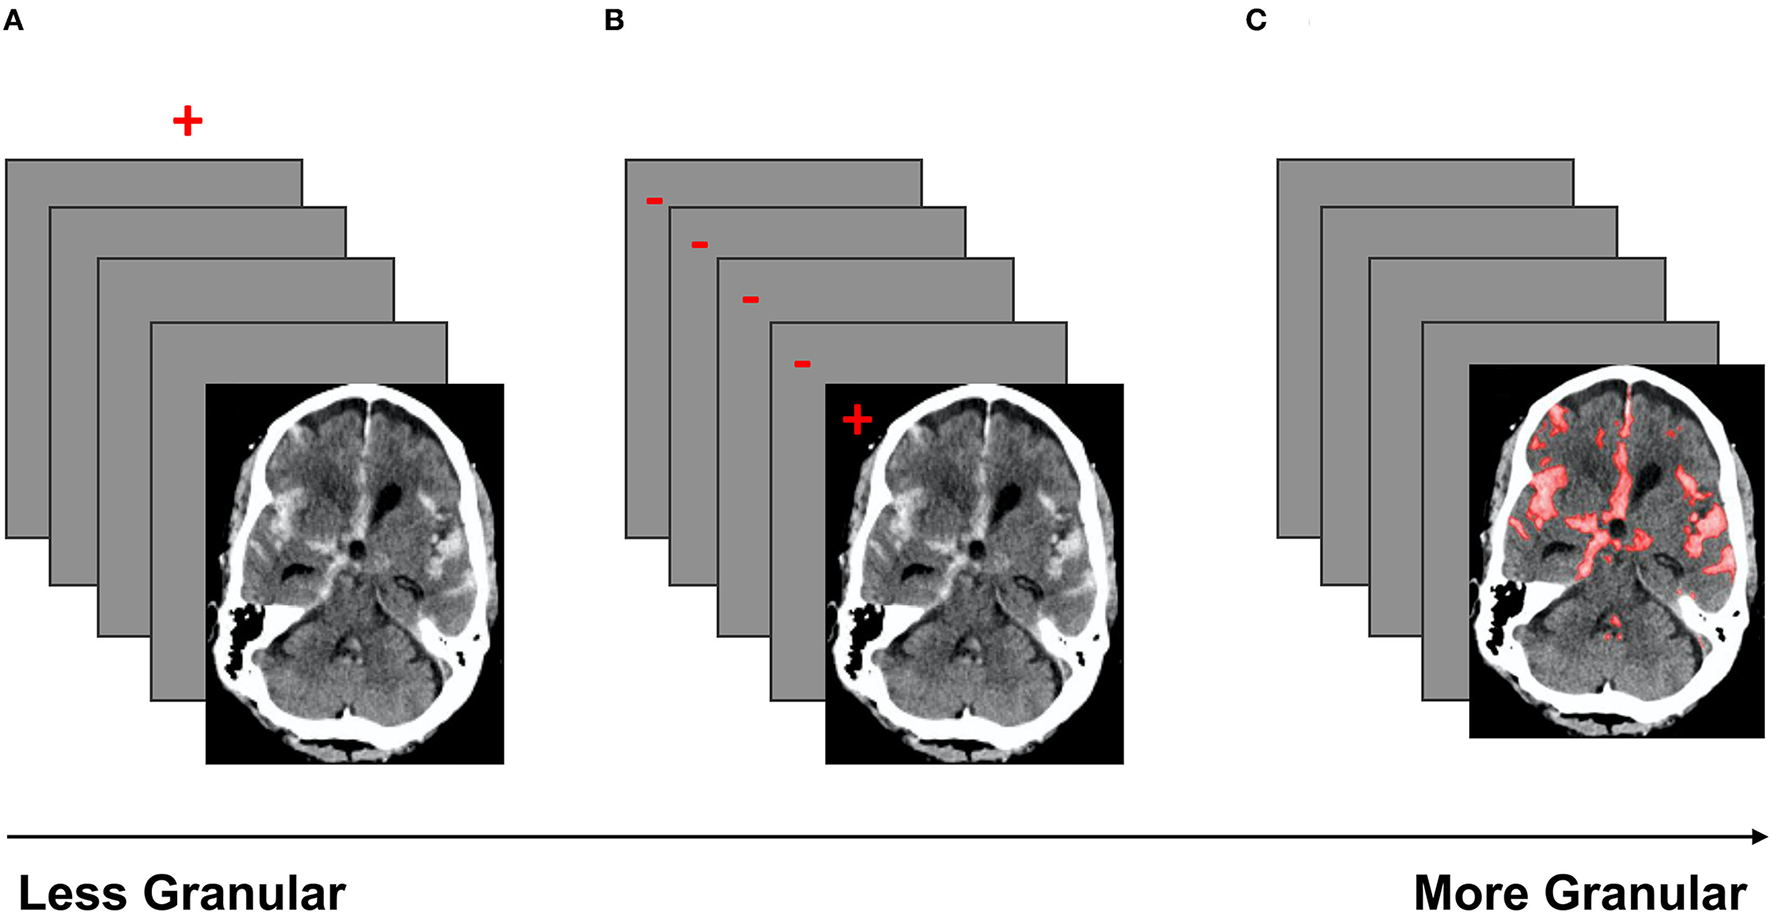

The coarsest data labeling strategy in medical imaging is examination-level labeling, which refers to categorization of each imaging exam based on the presence or absence of a specific type of imaging finding (Figure 4A). For example, a head CT exam typically contains a stack of 25–70 images, depending on the size of the head and the specific imaging protocol. If a CT exam has at least one instance of intracranial hemorrhage on at least one image, the entire exam would be annotated as “positive” for intracranial hemorrhage. The use of examination-level labels has several advantages, the primary being that these labels can generally be obtained with less time and cost, making it possible to amass larger datasets. In addition, examination-level labels can potentially be extracted from pre-existing clinical radiological reports by human reviewers without specialized training in radiology, or through the use of automated natural language processing algorithms. Examination-level labels represent the coarsest level of labeling and generally do not provide information on the location or size of abnormal findings.

Figure 4

A schematic of three labeling strategies in order of increasing granularity. Red indicates the label(s). (A) Demonstrates examination labels, in which an entire exam is annotated as “positive” or “negative” for a given pathology. (B) Demonstrates image labels, where each image in a stack is annotated as “positive” or “negative” for a pathology. (C) Demonstrates pixel labels, where all pixels in the exam are labeled as “positive” or “negative” (29).

Image-level annotations are an example of labels with an intermediate level of granularity. In this strategy, each image of an exam is annotated for the presence or absence of a specific type of imaging finding (Figure 4B). Unlike examination-level labels, image-level annotations provide some localization information, identifying the image(s) that contain instances of the finding of interest. Image-level labels provide significantly more information than examination-level labels, and can be used to improve the accuracy of exam-level predictions, as well as to provide coarse estimates of the locations and sizes of instances of the imaging finding of interest. However, image-level labels require significantly more cost and effort to obtain. Unlike examination labels, which are already present in clinical reports, image labels do not exist in the clinical setting and must be manually annotated by highly trained specialists.

Pixel-level annotation is the most granular labeling approach, and consists of the designation of each pixel in each image of the exam as positive or negative for the finding of interest. Pixel-level labels provide the densest information content (Figure 4C), and can be used to further improve the accuracy of exam-level predictions, as well as provide fine-grained localization information. Algorithms trained on high-quality pixel-level annotations have the potential to produce the strongest results because they are trained on the data with the densest information content. The primary disadvantage of this strategy is that pixel labels are costly and time-consuming to obtain, requiring manual delineation (“segmentation”) of the boundaries of each lesion or finding of interest. This is not a task that radiologists are accustomed to performing in a clinical setting, and is highly labor-intensive even with the use of optimized manual segmentation tools. Unlike examination-labeled datasets, the expansion of an existing pixel-labeled dataset may be prohibitively costly due to the labeling requirement. Regardless, algorithms trained on pixel labeled data can create stunning delineations of the boundaries of lesions, producing detailed location and size information that can be useful for clinical management decisions.